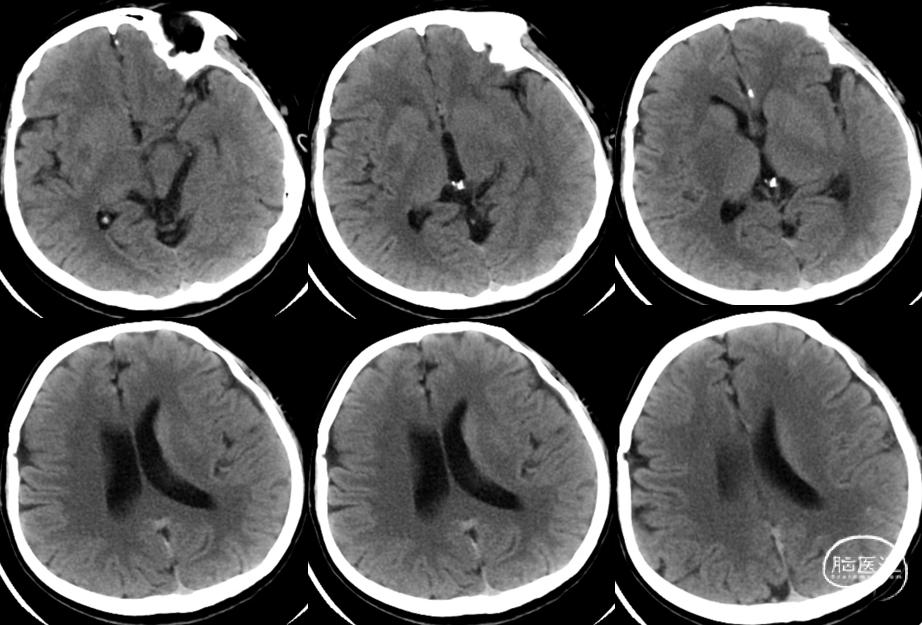

入院时CT:ASPECTS 9分(L1)。

术前MRI